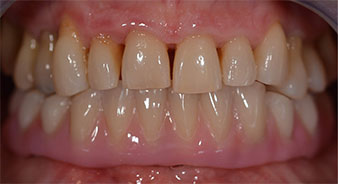

Una vez transcurrido el tiempo necesario para la integración ósea, puede llevarse a cabo la impresión definitiva del implante para realizar la prótesis definitiva de manera acorde (figs. 19 y 20). En este paso, el responsable del tratamiento y el paciente pueden decidir conjuntamente si es preferible un revestimiento cerámico o plástico y una estructura de zircón o de metal. En este caso, dado que el pronóstico de la dentición del maxilar superior era poco claro y la pieza dental 24 estaba elongada, el equipo del Dr. Pascu se decidió por un revestimiento de plástico, ya que, por lo general, es mucho más fácil de ajustar y puede adaptarse a la nueva situación del maxilar superior.

integración ósea

Fig. 19

Implantes

Fig. 20